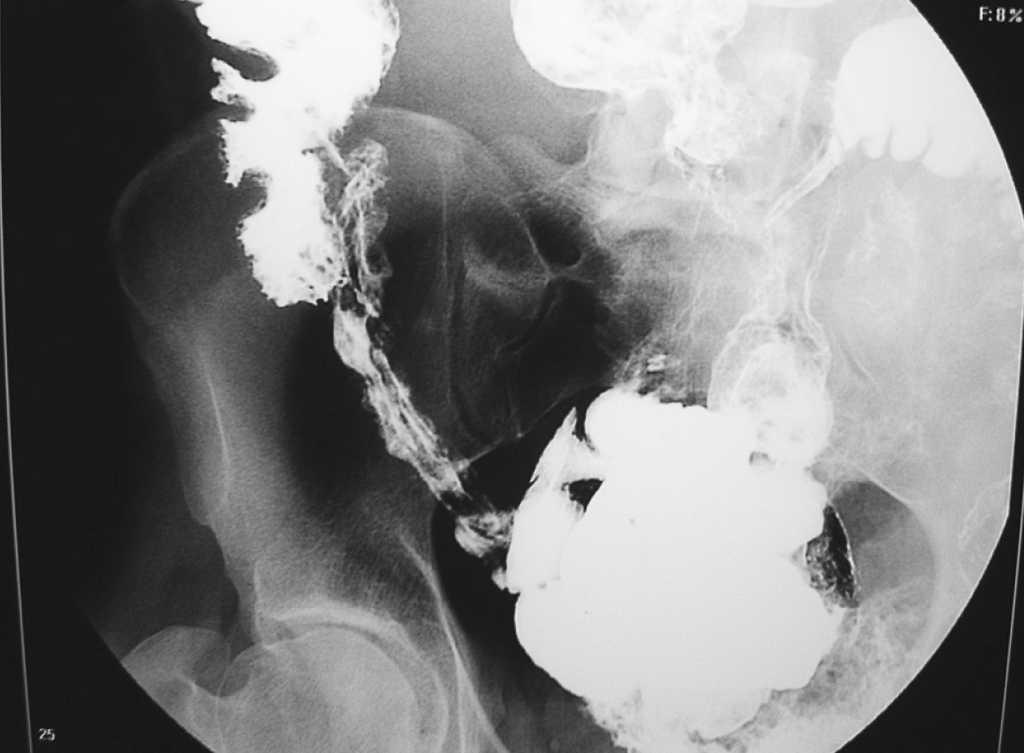

Se realizó colonoscopia, en colon izquierdo hasta ángulo esplénico se aprecian zonas edematosas salteadas, más continuas en descendente proximal. En algunas de ellas se aprecian pequeñas úlceras aftoides de 1 cm. Transverso distal poco afectado. Desde la mitad de trasverso hasta ángulo hepático se aprecia marcado edema de toda la mucosa salpicado de ulceras aftoides y serpiginosas de hasta 2 cm; siendo el diagnóstico endoscópico compatible con enfermedad de Crohn, confirmándose con las muestras tomadas para biopsia. Se solicita tránsito intestinal (fig. 2) donde aparece la afectación de íleon terminal.

Figura 2. Tránsito intestinal.